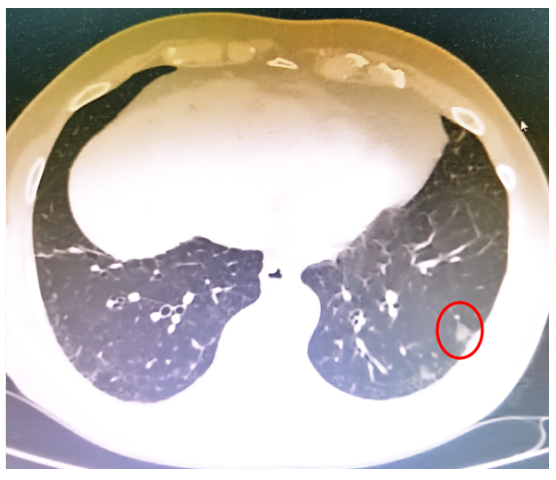

患者于2022年11月10日在全身麻醉下行左肺下叶部分切除+淋巴结活检术,手术过程顺利,入量1200 ml,尿量600 ml,出血10 ml。术后病理提示微浸润腺癌。术后顺利拔除气管插管,生命体征平稳。术后第3天开始出现活动后稍气喘,无明显发热,偶有咳嗽,咳白色黏痰。胸闷气喘症状逐渐加重。肝肾功能正常,D-二聚体正常,心肌标志物正常,未查血气和胸部CT;白细胞、CRP升高明显(表1)。予哌拉西林他唑巴坦+莫西沙星加强抗感染治疗。术后第5天胸部CT可见少量病灶(图2)。术后第12天胸部CT提示两肺间质性改变,右肺为著,局部可见支气管牵拉变形,磨玻璃影(图3)【普通感染不应出现如此变化,但当时并未引起重视】。后续患者出现呼吸衰竭,血气分析:pH 7.34,PaO2 53.1 mmHg,PaCO2 35.1 mmHg(面罩吸氧10 L/min)。转至ICU进一步治疗。

(1)感染性疾病:病毒性?细菌性?真菌?非典型病原体?吸入性肺炎?(2)非感染性疾病:心衰?急性肺栓塞?自身免疫性疾病?麻醉/手术相关肺损伤?急性间质性肺炎?回顾分析患者入院时胸部CT: 双肺靠近外周近胸膜处有轻微细小间质样改变(图4)。诊断:急性间质性肺炎;Ⅰ型呼吸衰竭;左肺下叶部分切除术后;高血压病。ECMO支持;呼吸机支持;甲泼尼松80 mg q12h,尼达尼布;镇静镇痛;抗感染;营养支持。ECMO第6天, 术后第18天, 肺部病变进一步加重(图5)。血气分析: pH 7.543, PaO2 154 mmHg, PaCO2 33.2 mmHg(ECMO, FiO2 100%, MV FiO2 60%)。术后第26天复查胸部CT未见改善。患者最终死亡。笔者团队也曾接诊过一例早期肺癌患者,2013年和2014年随访肺部结节均无明显变化。2015年胸部手术后2天,两肺变白(图6)。当时医生警惕性非常高,立刻行胸部CT检查并予相应治疗,患者最终存活。2022年RadioGraphics 杂志报道一例85岁女性腺癌患者奥希替尼治疗5个月后。图7-A和B为治疗前胸部CT图像,可见右肺中叶有肿块(A中箭头)。胸膜下区域磨玻璃改变和网状结构(箭头)提示存在间质性肺异常(Interstitial Lung Abnormalities,ILA)。治疗5个月后的轴位CT图像显示肿块(C中白色箭头)、弥漫性磨玻璃改变和合并症(黑色箭头)。图源:Radiographics, 2022, 42(7):1925-1939.另一例66岁右上肺鳞癌患者,术前CT显示肿块(图8-A中箭头)位于肺右上叶。轻度磨玻璃改变(箭头),提示ILA,见于胸膜下区域。图8-C和D为术后CT,显示弥漫性磨玻璃样改变和实变(箭头),牵引性支气管扩张症(图8-C中箭头),也可见胸腔积液(图8-D中箭头)。图源:Radiographics, 2022, 42(7):1925-1939.